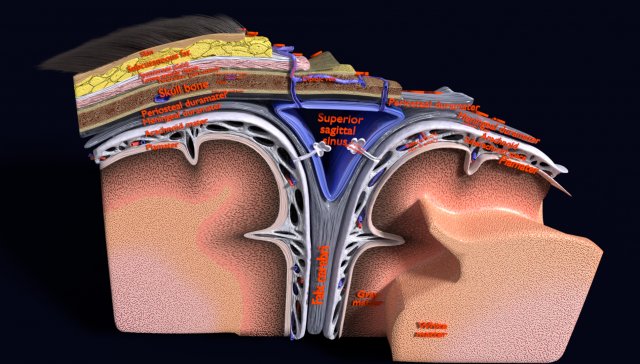

Brain with meninges scalp detailed labelled 3D 3D मॉडल

A blend model of brain along with its covering layers (meninges), skull bone and scalp labelled in detail and anatomically precise. The parts depicted are white, gray, pia, arachnoid, dura, bone, skin, fat, aponeurosis, periosteum, falx cerebri and more.

The material is high resolution image textures and normal maps based on non overlapping UVs. The texture and normal maps are packed with the blend file itself.